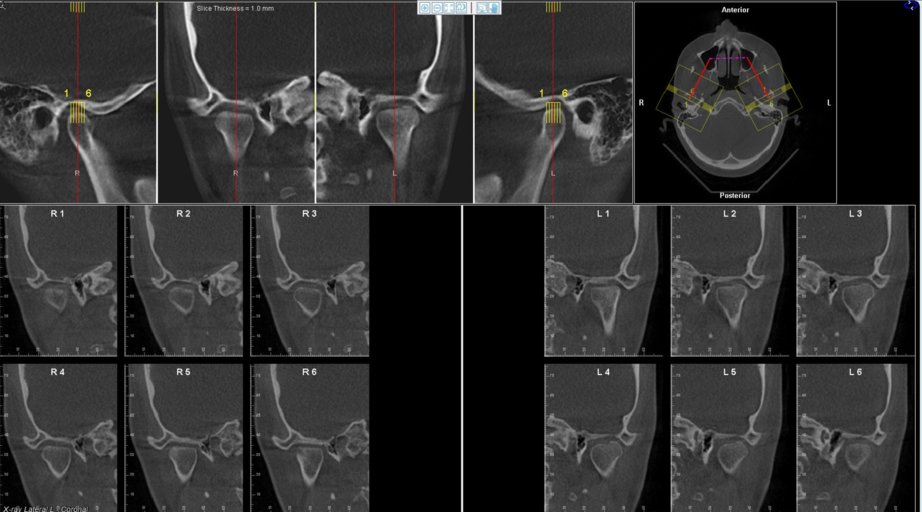

Attached is an image of my condyles. Are they normal and healthy or Do you see any bone loss such as flattening or erosion of them? If there does appear to be some bone loss, how does this affect my bite and the appearance/position of my jaw?? Is there any way to tell how long ago the bone loss occurred or if it is still active? Is there any way to get damaged condyles back to their previous state? (These are all questions I’m curious about the answers to even if my condyles end up appearing that they don’t have bone loss to you). Here is a link to a second image since it won’t let me upload more than one. https://ibb.co/jEowge

Attached is an image of my condyles. Are they normal and healthy or Do you see any bone loss such as flattening or erosion of them? If there does appear to be some bone loss, how does this affect my bite and the appearance/position of my jaw?? Is...